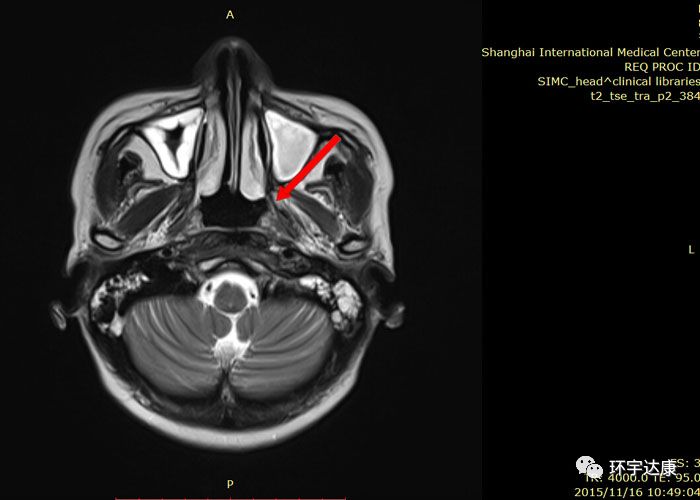

治疗期间,吴女士唾液分泌、皮肤、甲状腺无显著影响。治疗后MRI显示鼻咽左侧壁的局部复发已经明显缩小。两个月后吴女士开始正常上班。目前随访,病情处于稳定状态。